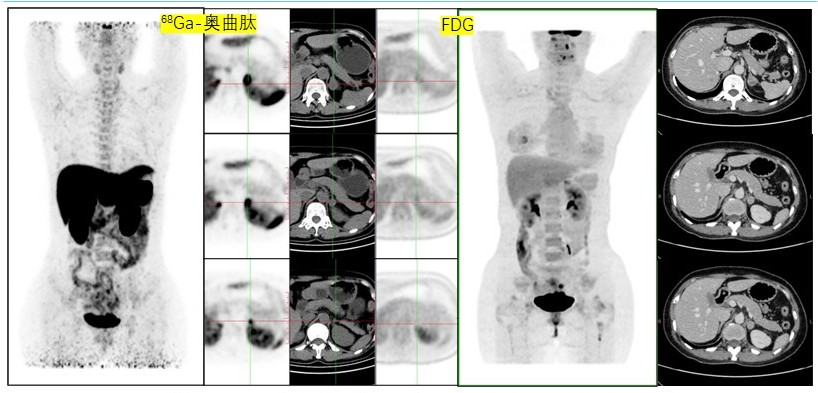

病例(13为一中年女性,间断心悸检查发现左肾上腺结节就诊,既往乳腺癌保乳术后;外院儿茶酚胺及其代谢产物检测提示多项指标升高,我院复查较前下降增强CT检查示左侧肾上腺三枚软组织密度结节伴中等强化;18F-FDG PET/CT68Ga-奥曲肽显像示三枚结节呈SSTR明显高表达、代谢无或轻度增高;(左肾上腺肿物)切除病理为节细胞神经瘤

13. 45岁,间断心悸2月余,发现肾上腺占位1月余节细胞神经瘤